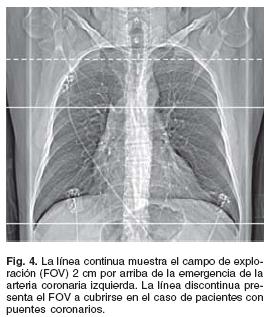

Antes de la administración del material de contraste (MC), se realiza el estudio en fase simple para determinar el campo de exploración (FOV, field of view) durante la fase contrastada, y se calcula el índice de Calcio (IC). El límite superior del FOV debe de estar 2 cm por arriba de la emergencia de las arterias coronarias y extenderse 2 cm por debajo del borde inferior del corazón. Típicamente se extiende desde el borde inferior de la carina hasta el diafragma (Fig. 4). En el caso de pacientes con puentes coronarios, el FOV debe de extenderse cranealmente hasta las clavículas 13 Por otro lado, si el IC es > 1.000 Unidades Agatston, no se recomienda continuar con la fase contrastada debido al alto índice de segmentos no valorables por la gran cantidad de placas calcificadas.32